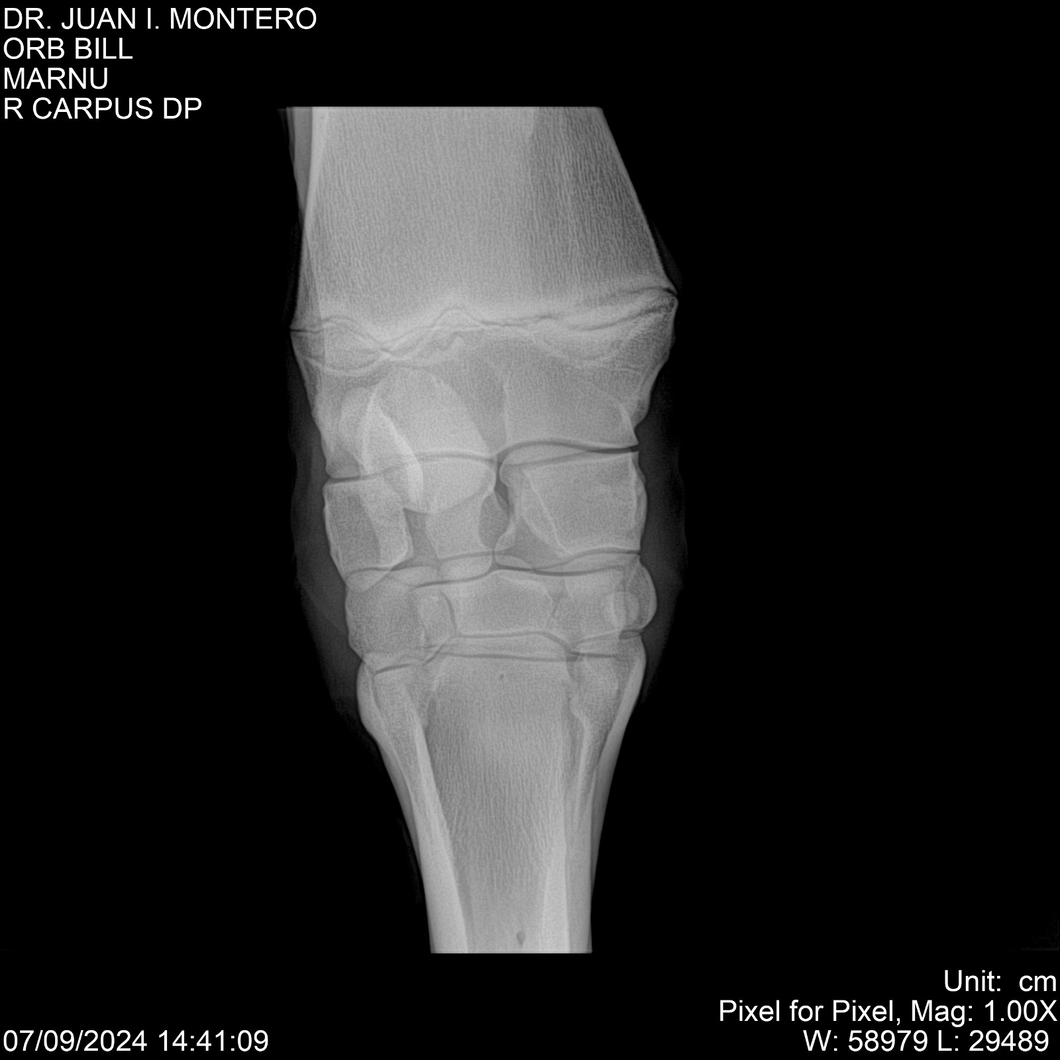

LOTE 7, ORB BILL 🔥 🔥 🔥 Lote Anterior Volver al remate Lote Siguiente Ficha Contacto Montevideo - Ficha del Lote Identificador: #282523 Categoría: Yeguarizos Montevideo - 83 Visualizaciones ClicData Contacto Empresa: Abelenda N. R., Walter Hugo Nombre*: Teléfono* : E-mail* : Mensaje Enviar Registrese gratis Este contenido Exclusivo está disponible sólo para usuarios registrados Ingresar